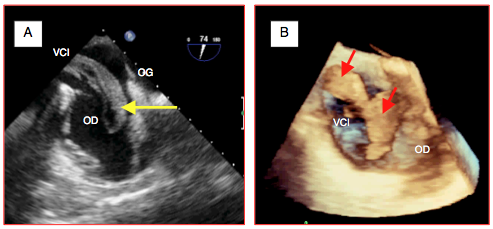

Figure 27.91 : Envahissement de la VCI et de l'OD par un hypernéphrome en vue bi-cave modifiée (A) et en reconstruction 3D (B).